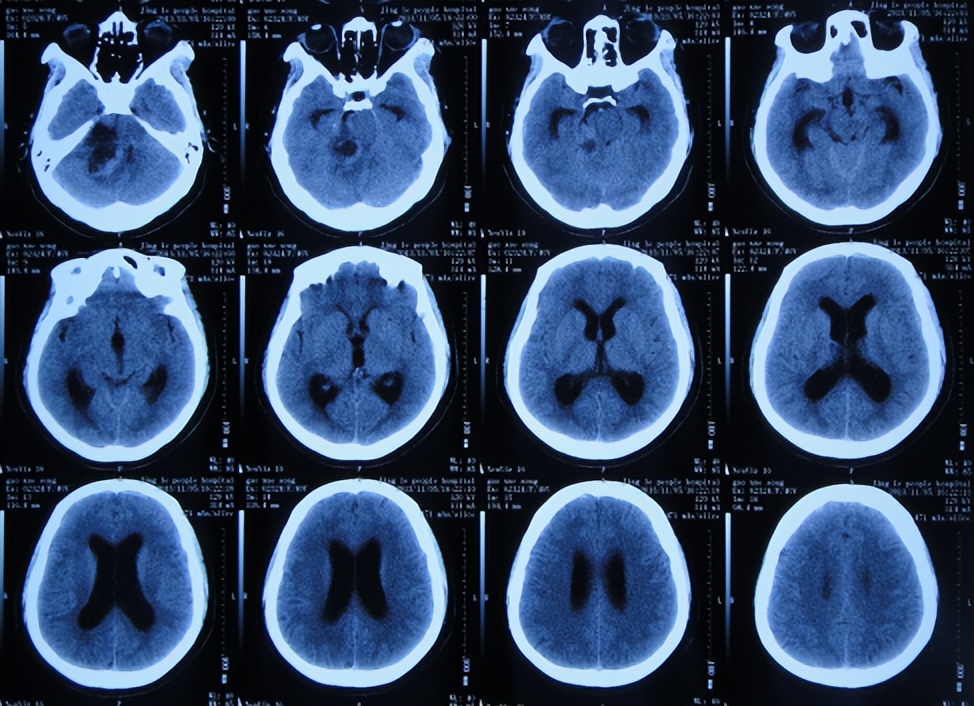

患者高老师是一名高中历史教师,右耳听力减退已10余年未给予特殊治疗,但2013年11月因出现病情严重的头疼头晕症状,到当地的山西省静乐县某医院,查头颅CT(图-1)后颅内肿瘤占位,需要手术。

图-1:2013年11月6日头颅CT